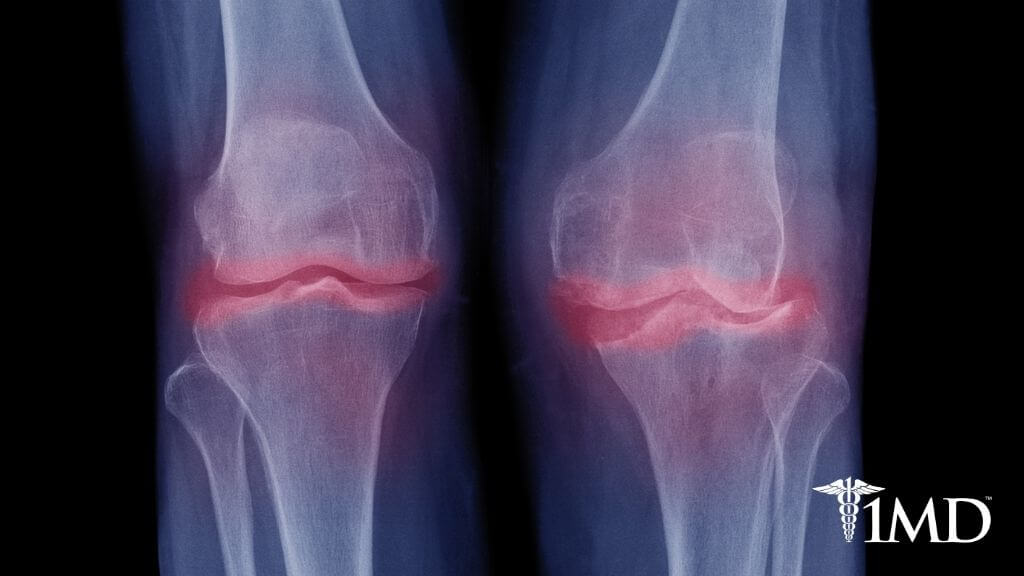

As we get older, our risk for arthritis also increases as the joints and bones naturally wear over time. Heavy use, previous injury, and aging cause your cartilage to break down, like the knees of a catcher in baseball.

This in turn causes your bones to rub together, causing pain and other notable symptoms. The prompt identification of these symptoms is essential for the prevention of more serious damage.